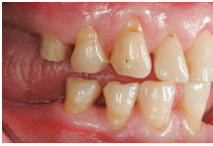

3、牙齿磨耗

牙齿磨耗的原因有很多,包括生理性磨耗,不良咀嚼习惯比如吃硬食;还有由于牙釉质、牙本质发育不良导致的牙齿不正常磨耗。这种磨耗会导致牙本质敏感,牙齿酸痛等情况,久而久之甚至会影响颞下颌关节的健康。有时候牙齿的不均匀磨耗会导致牙齿边缘锐利,刺激口腔黏膜;牙齿的不均匀磨耗也会增加镶牙的难度。牙齿磨耗的治疗策略是避免咀嚼硬食,若是因为氟斑牙或者四环素牙等导致牙釉质发育不好的,则请尽快就诊。